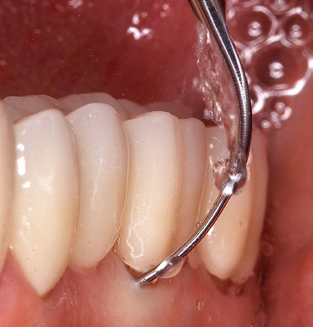

Following machine cleaning of the tooth and implant surfaces, the surfaces of the natural teeth are cleaned manually using standard hand instruments. When performing manual cleaning, particular attention must be given to maintaining the correct angle of application, appropriate sharpness, good support and working with the curette from apical to coronal. Either titanium or carbon curettes should be used for post-cleaning of the implant structures (Fig. 8). In addition to the use of ultrasonic devices, power jet devices can also be used in conservative dentistry. However, it must be taken into consideration that these procedures are not suitable for removing hard deposits and thus they cannot replace the use of hand instruments and ultrasonic instruments completely. In all cases, cleaning is followed by mechanical polishing of the accessible tooth and implant surfaces with polishing cups and polishing compounds (Fig. 9).